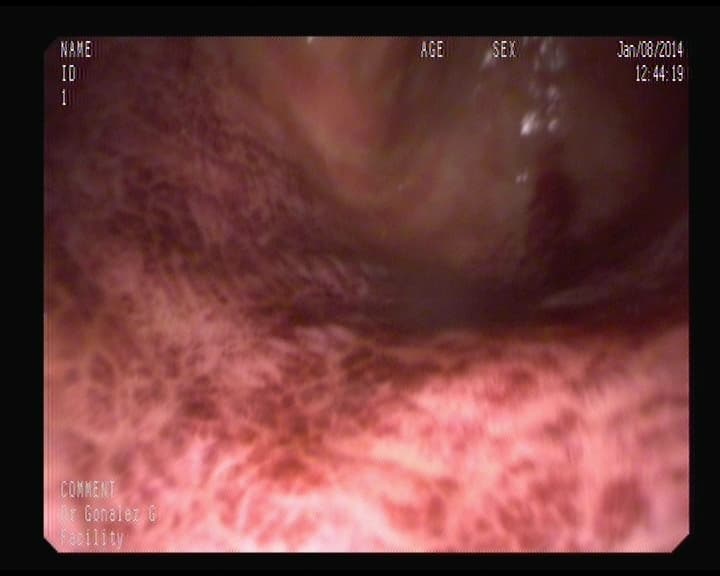

Punto sangrante anterior foto, ya solucionado.

Resultado del punto sangrante en duodeno ya tratado.